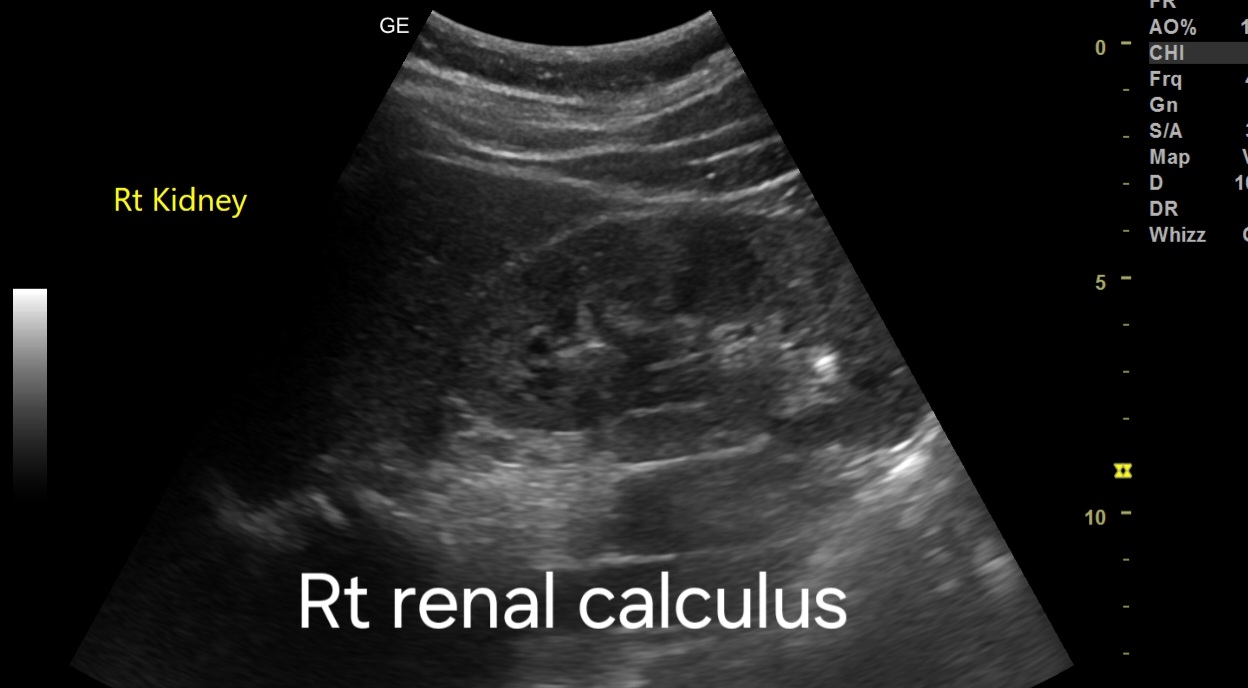

2. Small Renal Calculus:

- Ultrasound identifies a hyperechoic structure within the renal parenchyma measuring approximately [size], indicative of a small renal calculus.

- The calculus may cause posterior acoustic shadowing and may demonstrate twinkling artifacts on color Doppler imaging, aiding in its identification.

2. Renal Calculus:

- In cases where ultrasound findings are ambiguous or if further characterization is needed, a non-contrast CT scan of the abdomen and pelvis is recommended.

- CT scan provides superior visualization of renal calculi, allowing for accurate assessment of size, location, and composition.

- Dual-energy CT may be utilized to differentiate between types of renal calculi based on their composition, which can influence treatment decisions.

- Renal Calculus:

- Treatment options include conservative management, extracorporeal shock wave lithotripsy (ESWL), ureteroscopy with laser lithotripsy, or percutaneous nephrolithotomy (PCNL) depending on the size and location of the stone.

- Adequate hydration and dietary modifications may aid in the prevention of recurrent stones.

- Follow-up imaging may be necessary to monitor for stone progression or recurrence.